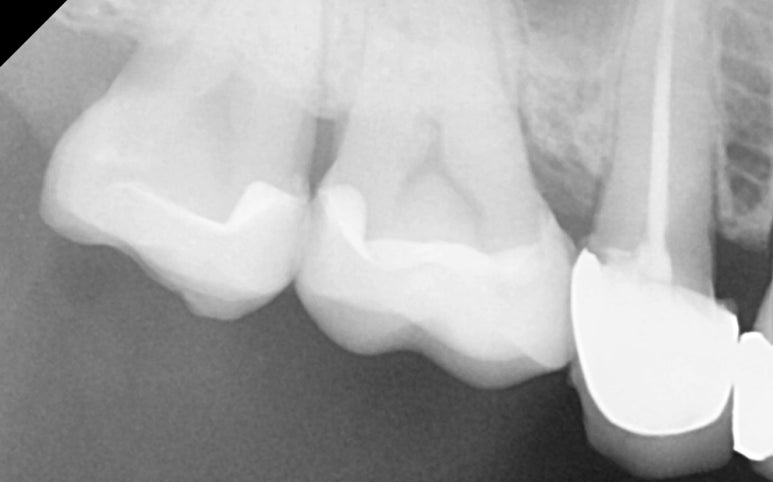

25.11.11 레진 코팅 후 엑스레이 사진

25.11.19 접착 후 엑스레이